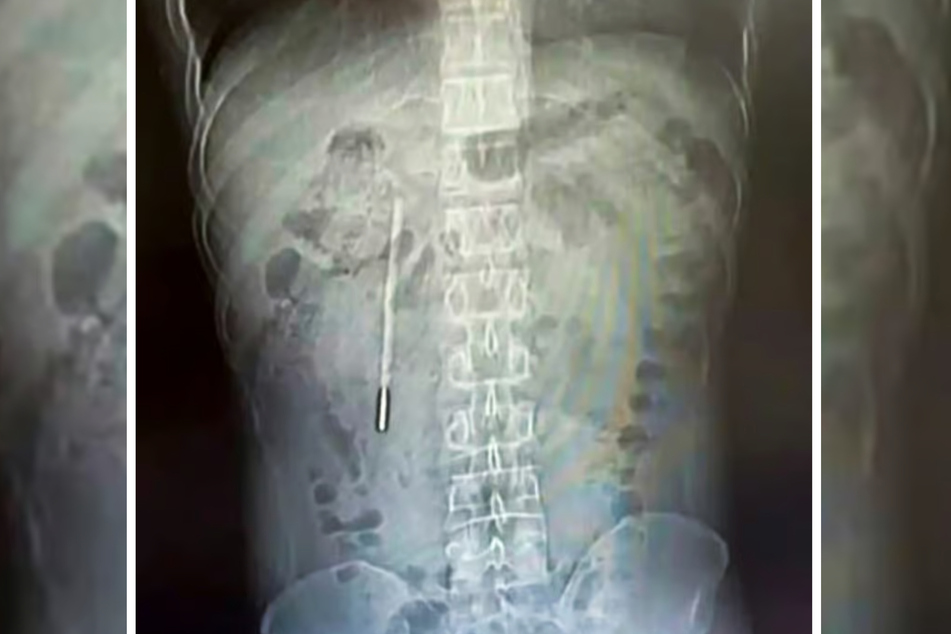

Als die Ärzte den Zwölffingerdarm des 32-Jährigen kontrollierten, stieß man auf einen Fremdkörper. Dieser sollte sich laut der South China Morning Post als ein Quecksilberthermometer entpuppen, dessen Spitze direkt gegen die Darmwand drückte.

Da man nicht ausschließen konnte, dass das Messgerät bereits Verletzungen oder gar innere Blutungen verursacht hatte, landete der Chinese direkt auf dem Operationstisch.

20 Minuten später war der merkwürdige Fremdkörper aus dem Körper des Patienten entfernt.

Der Eingriff gestaltete sich als kompliziert, da das Thermometer sehr nah an den Gallengängen des Mannes gelegen hatte.